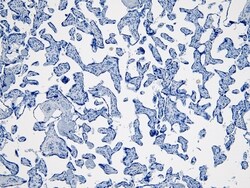

Aplicaciones Immunohistochemistry (Paraffin), Western Blot